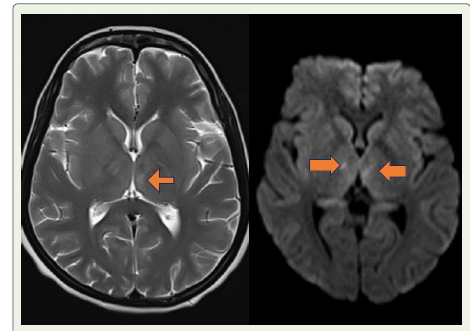

The extrapyramidal signs—including rubral tremors, rigidity,

and dystonia—suggest involvement of the basal ganglia or midbrain

tegmentum, a region frequently implicated in EBV encephalitis, as

documented in case series and radiological reviews. Opsoclonus

and dysarthria point toward cerebellar and brainstem involvement.

Behavioural disturbance like altered sensation and mood disturbance

suggests the involvement of thalamus (supratentorial region).

• S Vyas et al. (2020) summarized radiological manifestations of EBV encephalitis, noting basal ganglia and thalamic involvement as key MRI features, consistent with our patient’s clinical profile. [14]